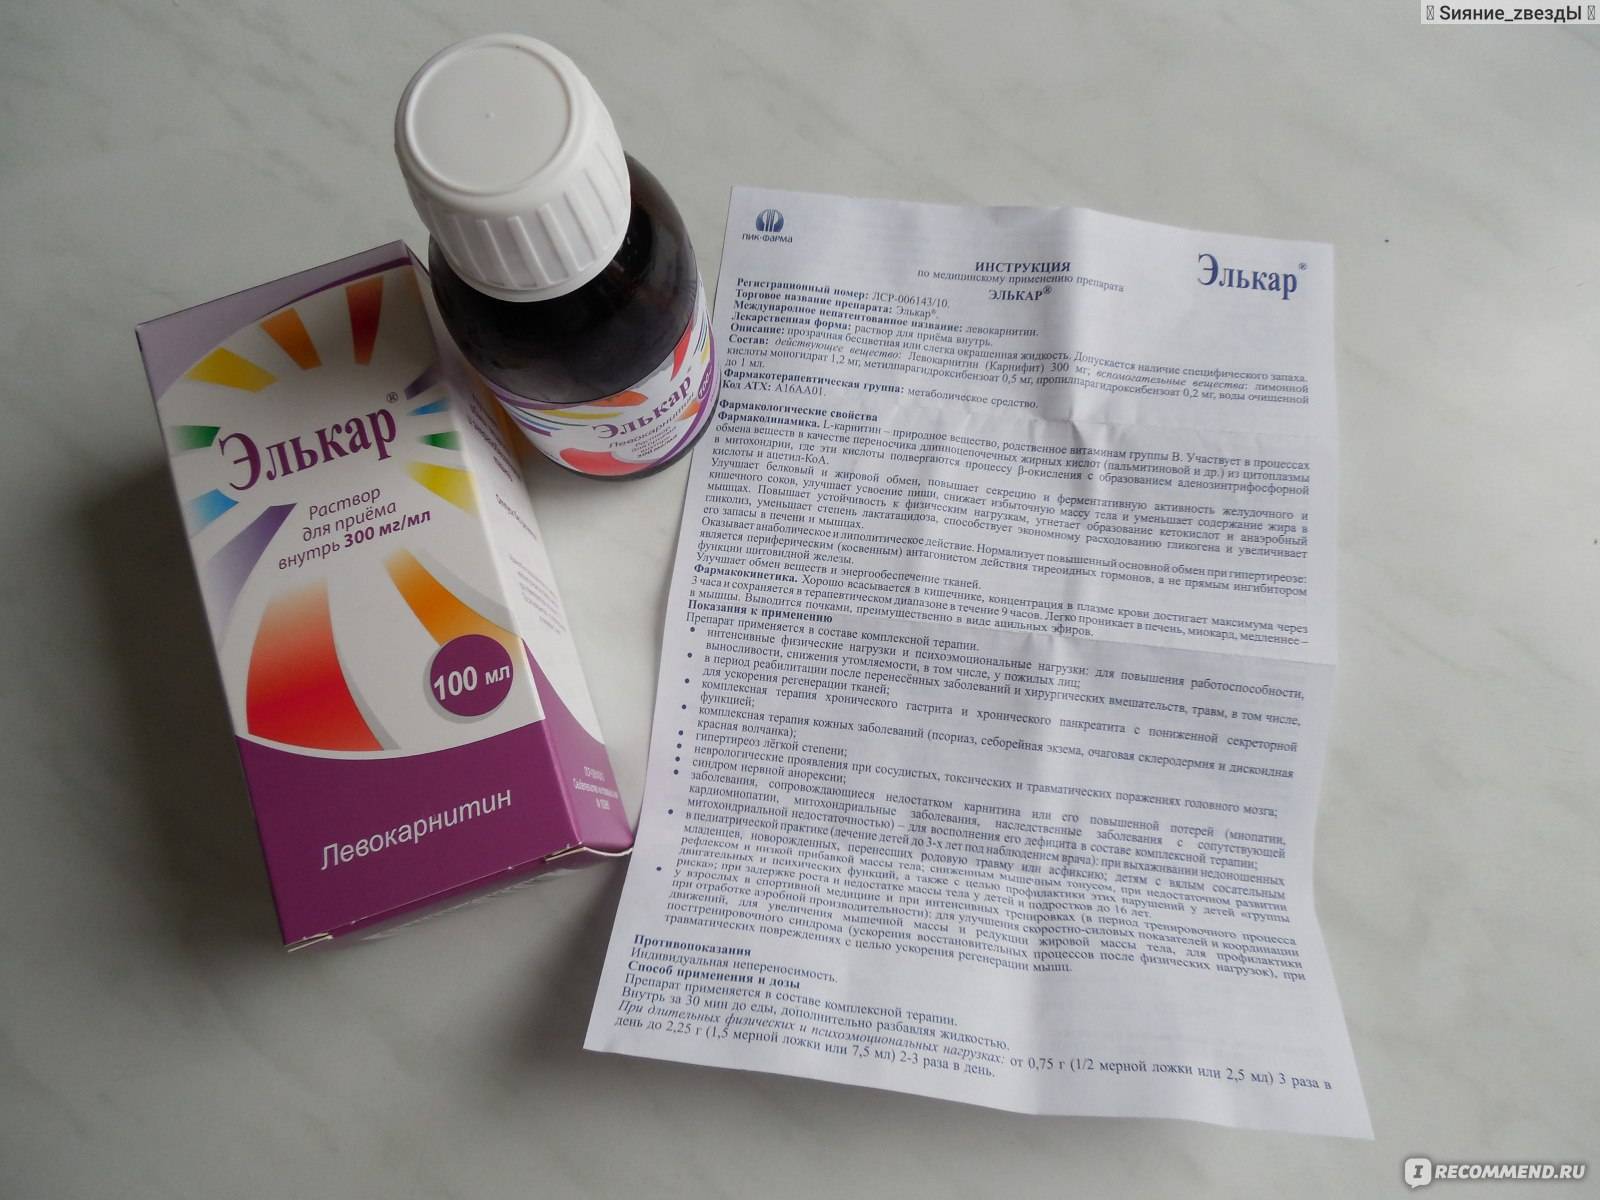

Препарат Элькар содержит L-карнитин (природное вещество) и вспомогательные вещества – сорбиновую кислоту и воду.

Элькар инструкция по применению и общее описание препарата

Средство традиционно выпускается во флаконах темного стекла объемом от 25 до 100 мл, к которым может прикладываться мерная ложка или мерный стаканчик. С учетом особенностей дозировки, даже самого маленького флакона хватит на полноценный курс для взрослого человека, впрочем, зависит это и от способа применения.

- Активное действующее вещество — карнифин, известный как L-карнитин, вспомогательные компоненты — лимонная кислота, вода.

Показания к применению

Препарат применяется в составе комплексной терапии.